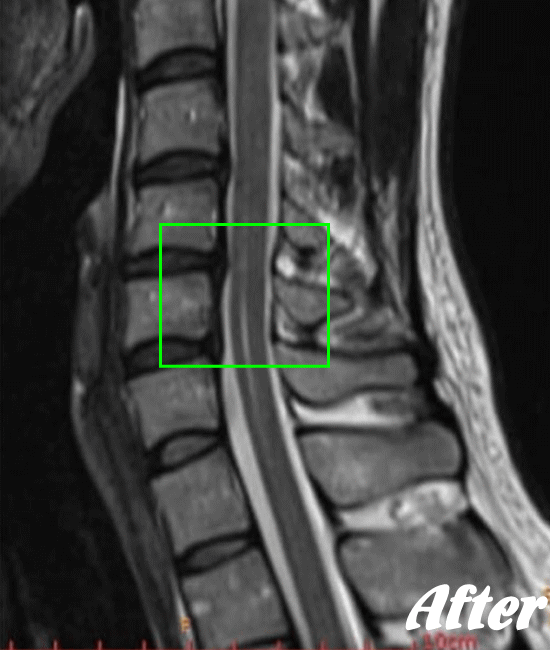

HALOカイロプラクティック☆平和島整体院では、骨盤から背骨全体(腰椎、胸椎、頸椎)を調整し、肩甲骨の動きを柔軟にし、首周りの筋肉をゆるめ、頚椎の骨と骨との間隔を広げ、動きを滑らかにして、首の負担を軽減させながらバランスを整える施術を行います。

頚椎症は、速効矯正・即効施術の【体の整体】の適応になります。

施術で痛みや痺れがとれても、普段から姿勢を気を付けていただかないことには、再発する可能性は高いので、セルフケアは是非行ってください。

もし、いつまで経っても一向に回復の兆しが見られないとお悩みなら、是非、HALOカイロプラクティック☆平和島整体院へお気軽にご相談ください。